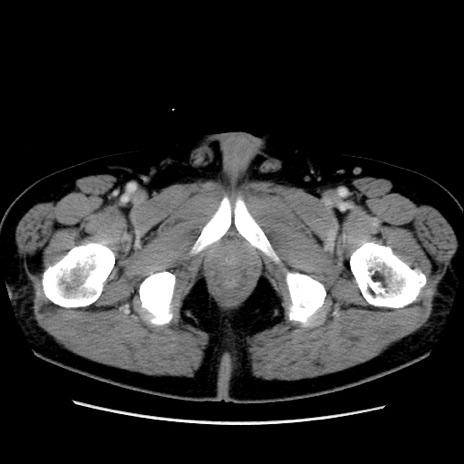

症例16(横断像)

【症例】 70歳代男性

【主訴】 腹痛、嘔吐

【現病歴】 約1ヶ月前より間欠的に腹痛と嘔吐あり、当院消化器内科を受診したところCTで多発する肝臓のLDAを指摘され、精査中であった。以降は消化器症状は安定していたが、2日前より嘔気と腹痛があり、同日より排便・排ガスが消失した。改善認めず、 本日、救急外来を受診した。

【既往歴】 大腸ポリープ切除後。

【身体所見】意識清明・会話良好、BT 36.3℃、BP 127/80mmHg、 P 80bpm、腹部:膨満あり、平坦・軟、上腹部正中および下腹部正中に圧痛あり、反跳痛なし、筋性防御なし。

【データ】WBC 7200、CRP 0.77